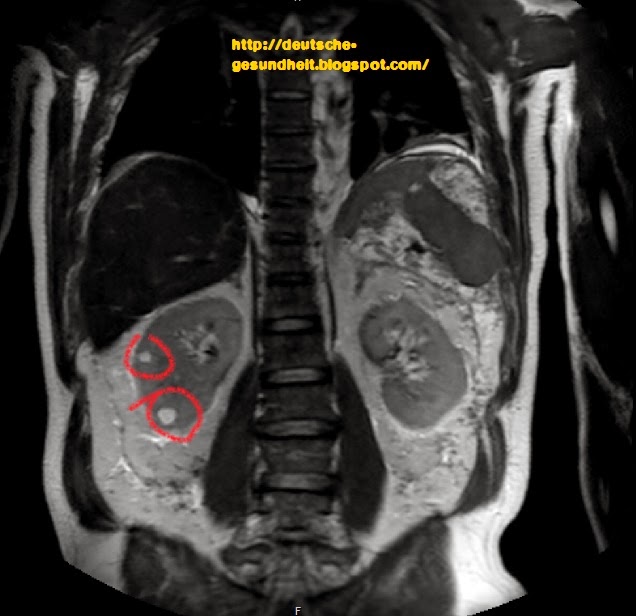

MRT Niere 8 – DocCheck North-East Line map – Singapore MRT

MRT Niere3 – DocCheck MRT Übersichtsaufnahme – DocCheck

Medizin – Gesundheit: Nierenzysten in MRI Abdomen medizinisches Bild Vorhofseptumdefekt (MRT) – DocCheck

MRT abdomen – DocCheck MRT Knie links

MRT Nieren – DocCheck MRT Knie links